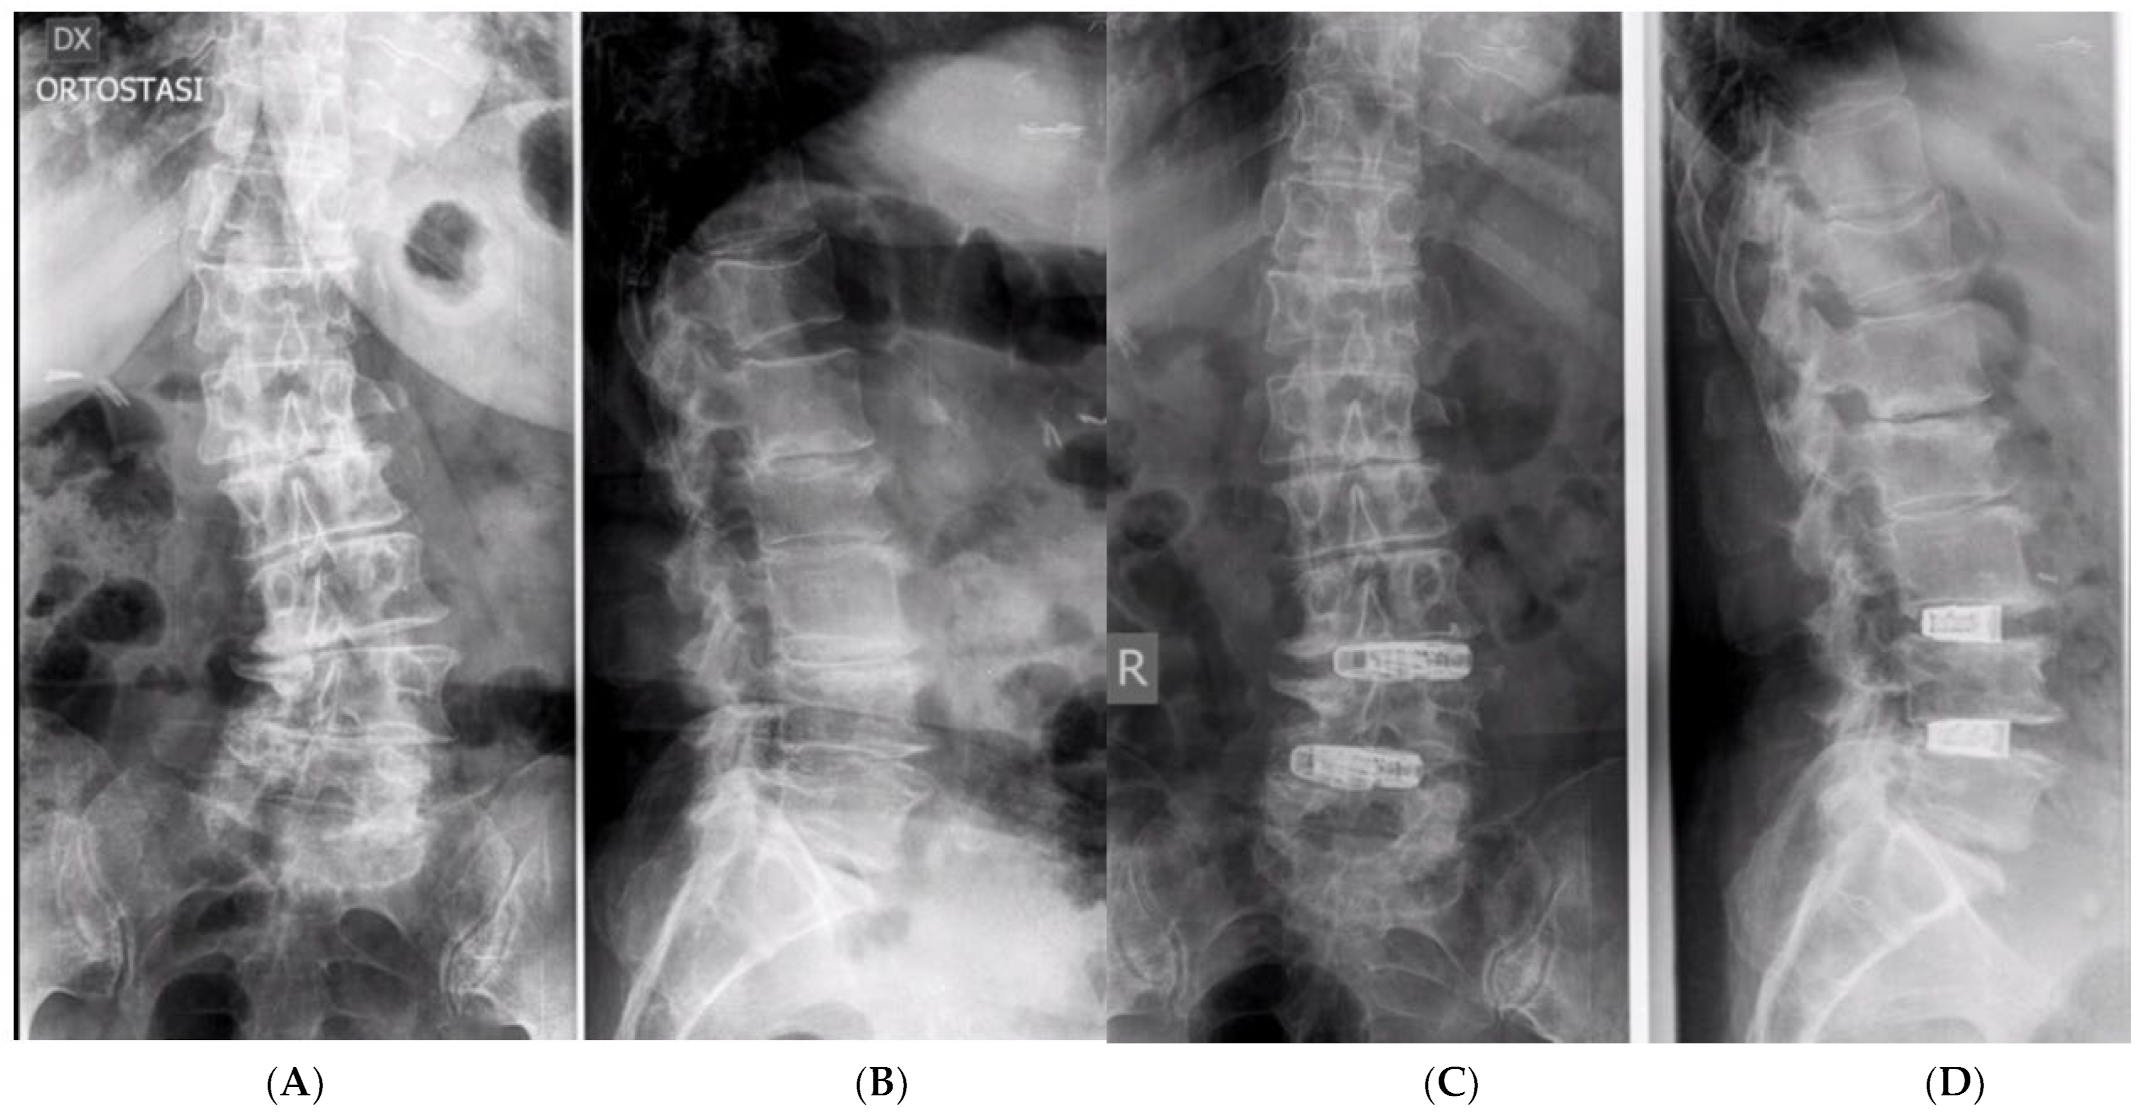

3.2. Clinical and Radiological Outcomes